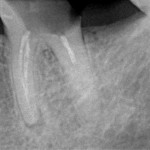

Прицельный радиовизиографический снимок можно сделать в любой из наших клиник. В отличие от обычных прицельных рентгенограмм зубов, доза лучевой нагрузки при проведении подобного исследования в несколько раз ниже, поэтому таких снимков можно сделать очень много. Например, по существующим стандартам, терапевт стоматолог может сделать до десяти снимком зуба в процессе эндодонтического лечения — и это, разумеется, необходимо для качественного лечения каналов зубов.

В хирургической практике я использую прицельные снимки как для первичной диагностики: например, чтобы быстро понять локализацию ретинированного зуба мудрости и его отношение к окружающим структурам, либо для интра- и послеоперационного контроля результатов имплантологического лечения. А наличие цифровой базы радиовизиографических снимков позволяет понять, как ведет себя протез на импланте в течение длительного времени: